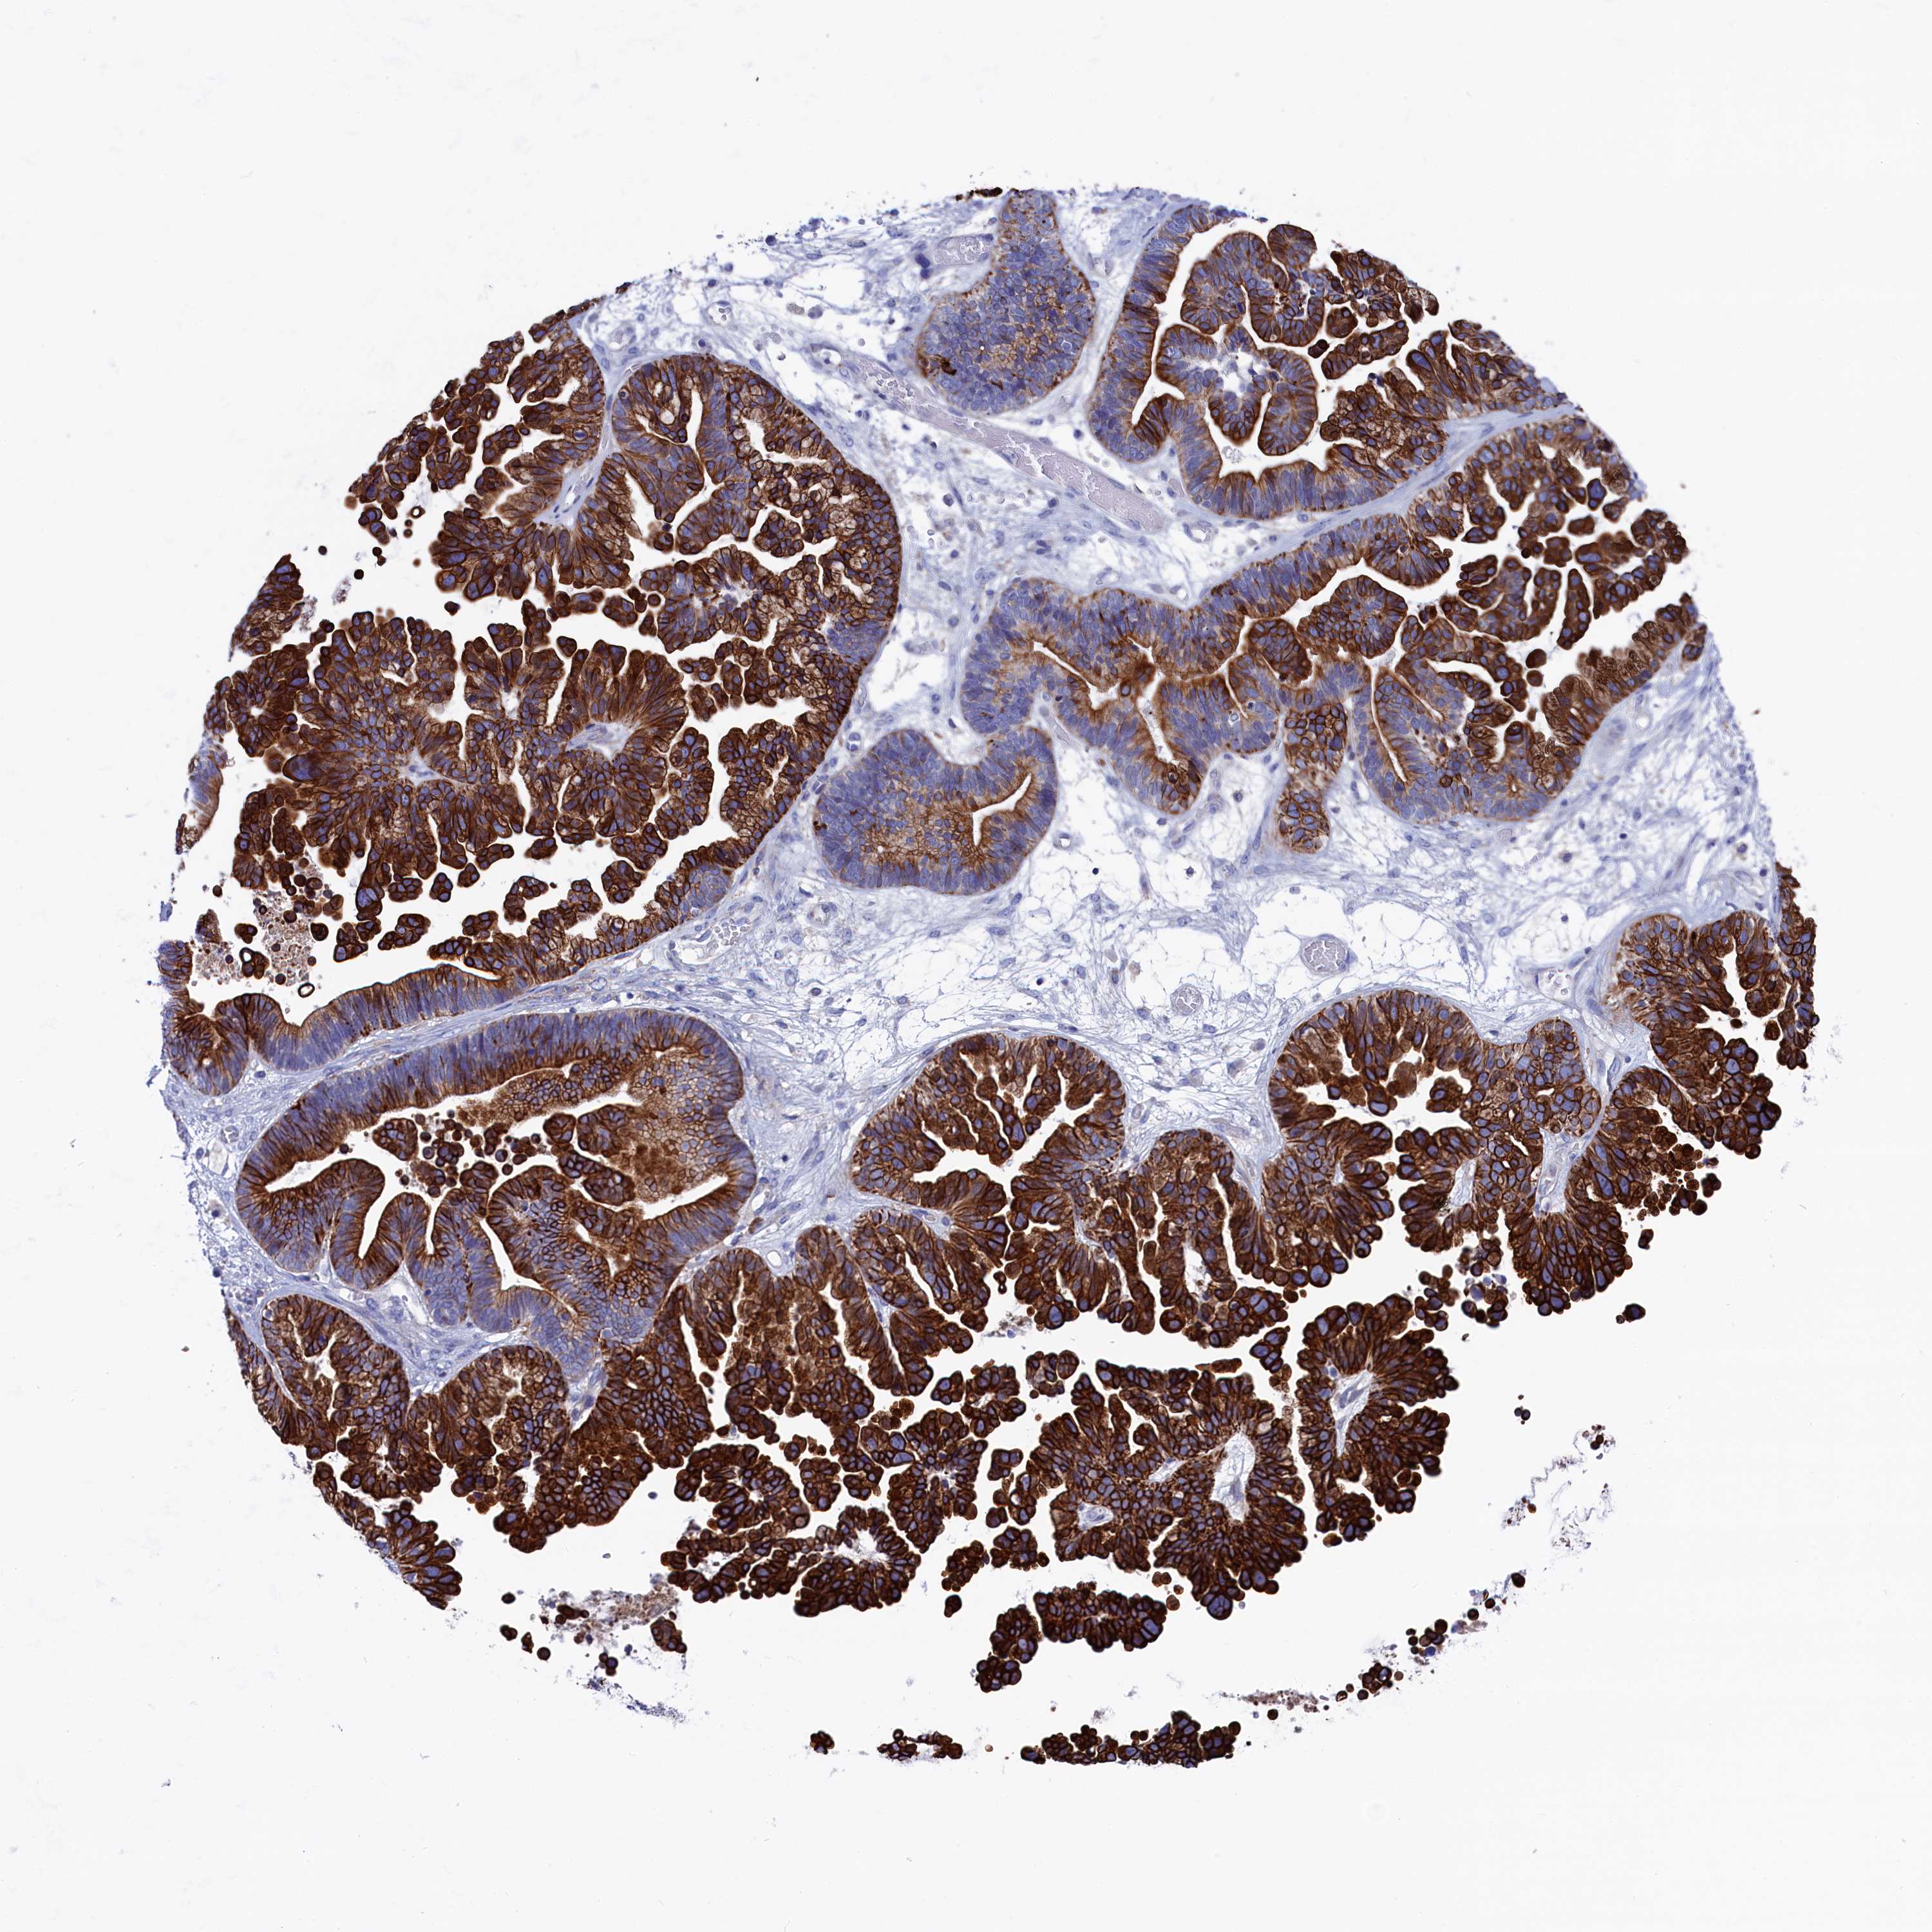

OVARIAN CANCER - Protein expressioni

A mouse-over function shows sample information and annotation data. Click on an image to view it in a full screen mode. Samples can be filtered based on level of antibody staining by selecting one or several of the following categories: high, medium, low and not detected. The assay and annotation is described here.

Note that samples used for immunohistochemistry by the Human Protein Atlas do not correspond to samples in the TCGA dataset.

Antibody stainingi

Antibody staining in the annotated cell types in the current human tissue is reported as not detected, low, medium, or high, based on conventional immunohistochemistry profiling in selected tissues. This score is based on the combination of the staining intensity and fraction of stained cells.

Each image is clickable and will lead to virtual microscopy that enables deeper exploration of all samples and also displays staining intensity scores, fraction scores and subcellular localization as well as patient and tissue information for each sample.

Antibody HPA042042

Staining

High

Medium

Low

Not detected

Intensity

Strong

Moderate

Weak

Negative

Quantity

>75%

75%-25%

<25%

None

Location

Nuclear

Cytoplasmic/membranous

Cytoplasmic/membranous,nuclear

Cystadenocarcinoma, serous, NOS

Carcinoma, endometroid

Cystadenocarcinoma, mucinous, NOS

Carcinoma, NOS